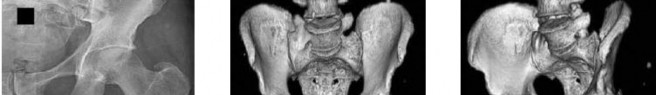

A 31-year-old man sustained an unstable closed left posterior hip dislocation in a motorcycle accident. A postreduction radiograph is shown in Figure 51a. 3-D CT scans are shown in Figures 51b and 51c. What is the optimal surgical approach that will allow for the most appropriate treatment?